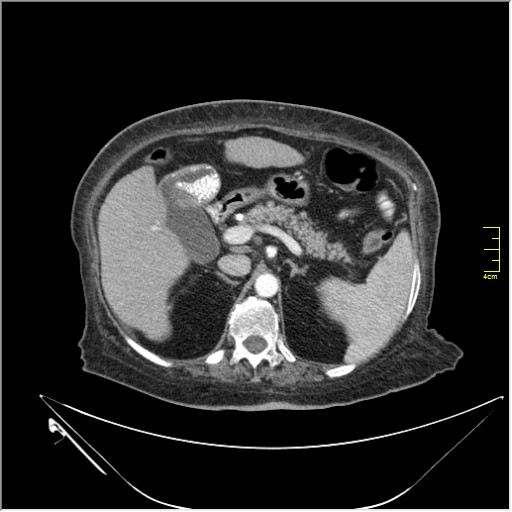

образование в правом надпочечнике

Incedentaloma правого надпочечника

Оценить нативную плотность и динамику вымывания контраста.

При данных за доброкачественный характер - наблюдение (возможно динамическое УЗИ).

При недоброкачественном паттерне -поиск первичного очага, биопсия надпочечника.

Находки 2:

1.Образование правого надпочечника с плотностью жира, липома. Ничего делать не надо. По другим вариантам incidentalomas, Др. Капустин всё расписал.

2. Множество мелких конкрементов жёлчного пузыря, заполняющие до 50% просвета. С этим надо что-то делать. )))